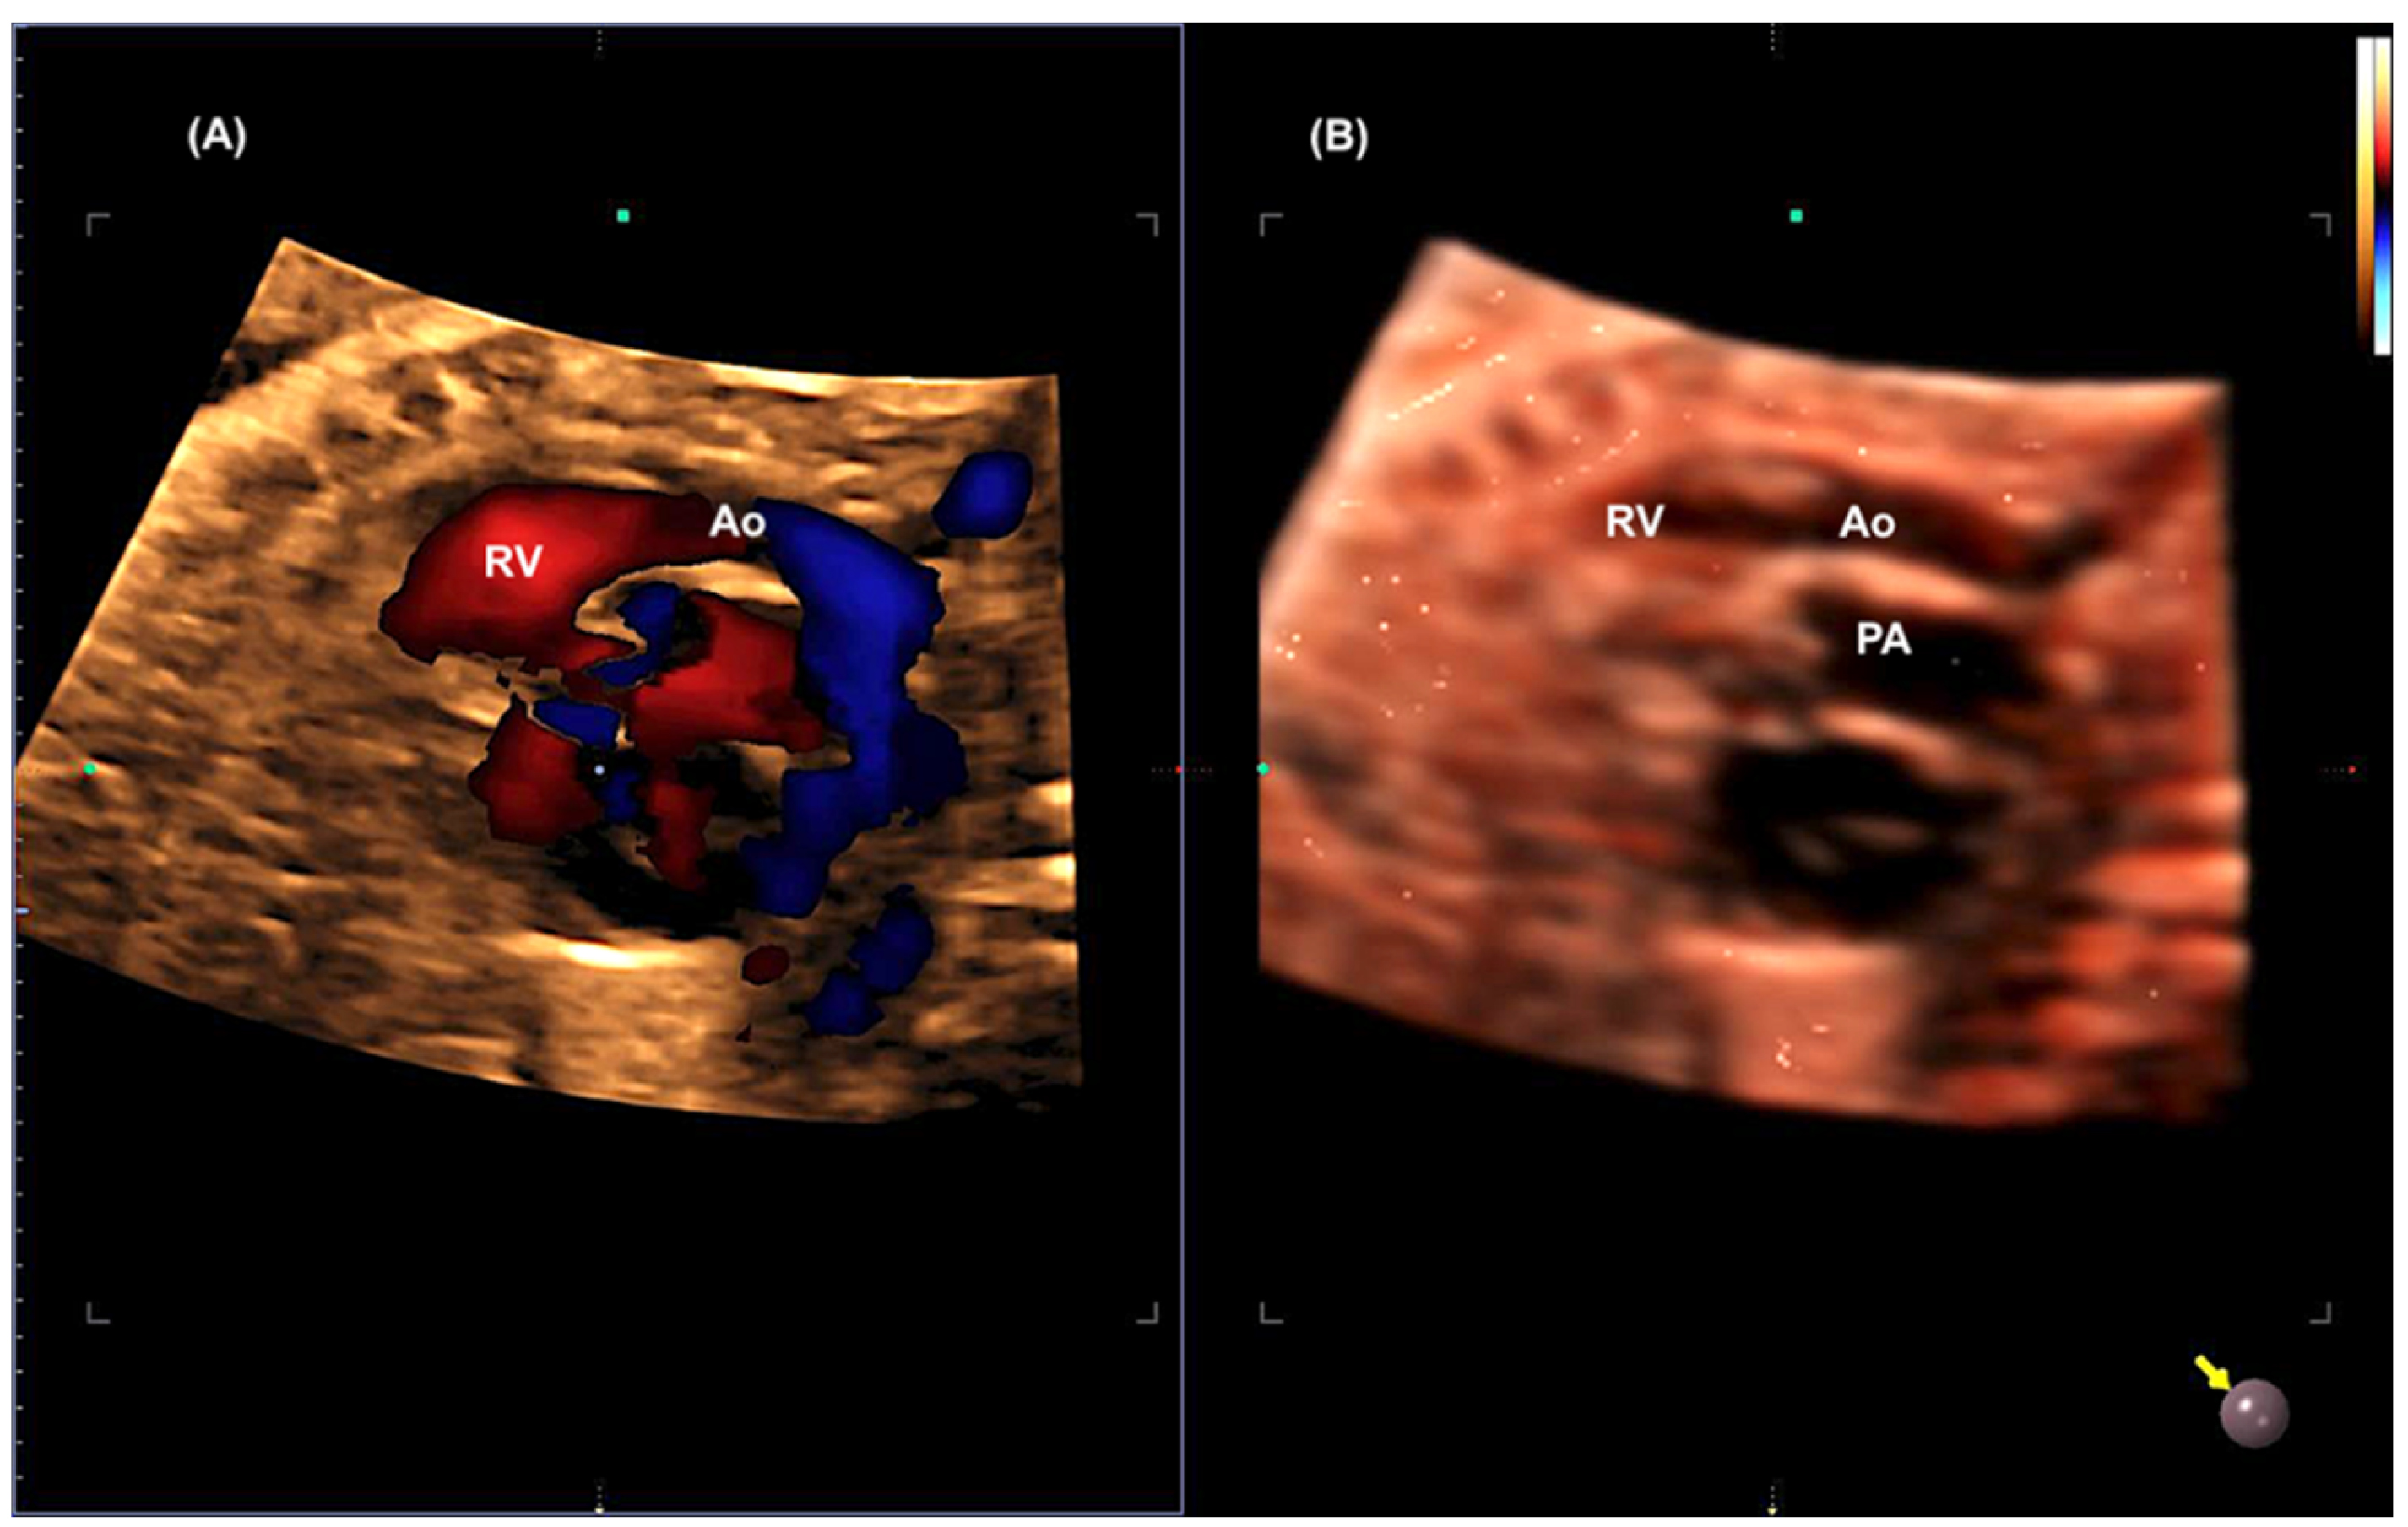

- Malho AS, Bravo-Valenzuela NJ, Ximenes R, Peixoto AB, Araujo Júnior E. Antenatal diagnosis of congenital heart disease by 3D ultrasonography using spatiotemporal image correlation with HDlive Flow and HDlive Flow silhouette rendering modes. Ultrasonography. 2022, 41, 578–596.

- Araujo Júnior E, Tonni G, Bravo-Valenzuela NJ, Da Silva Costa F, Meagher S. Assessment of Fetal Congenital Heart Diseases by 4-Dimensional Ultrasound Using Spatiotemporal Image Correlation: Pictorial Review. Ultrasound Q. 2018, 34, 11–17.

- Malho A, Ximenes RS, Bravo-Valenzuela NJ, Araujo Júnior E. Spatio-Temporal Image Correlation: Three-Dimensional Imaging for Fetal Cardiac Screening and Congenital Heart Disease Assessment. Arq Bras Cardiol. 2024;121(4):e20230580.